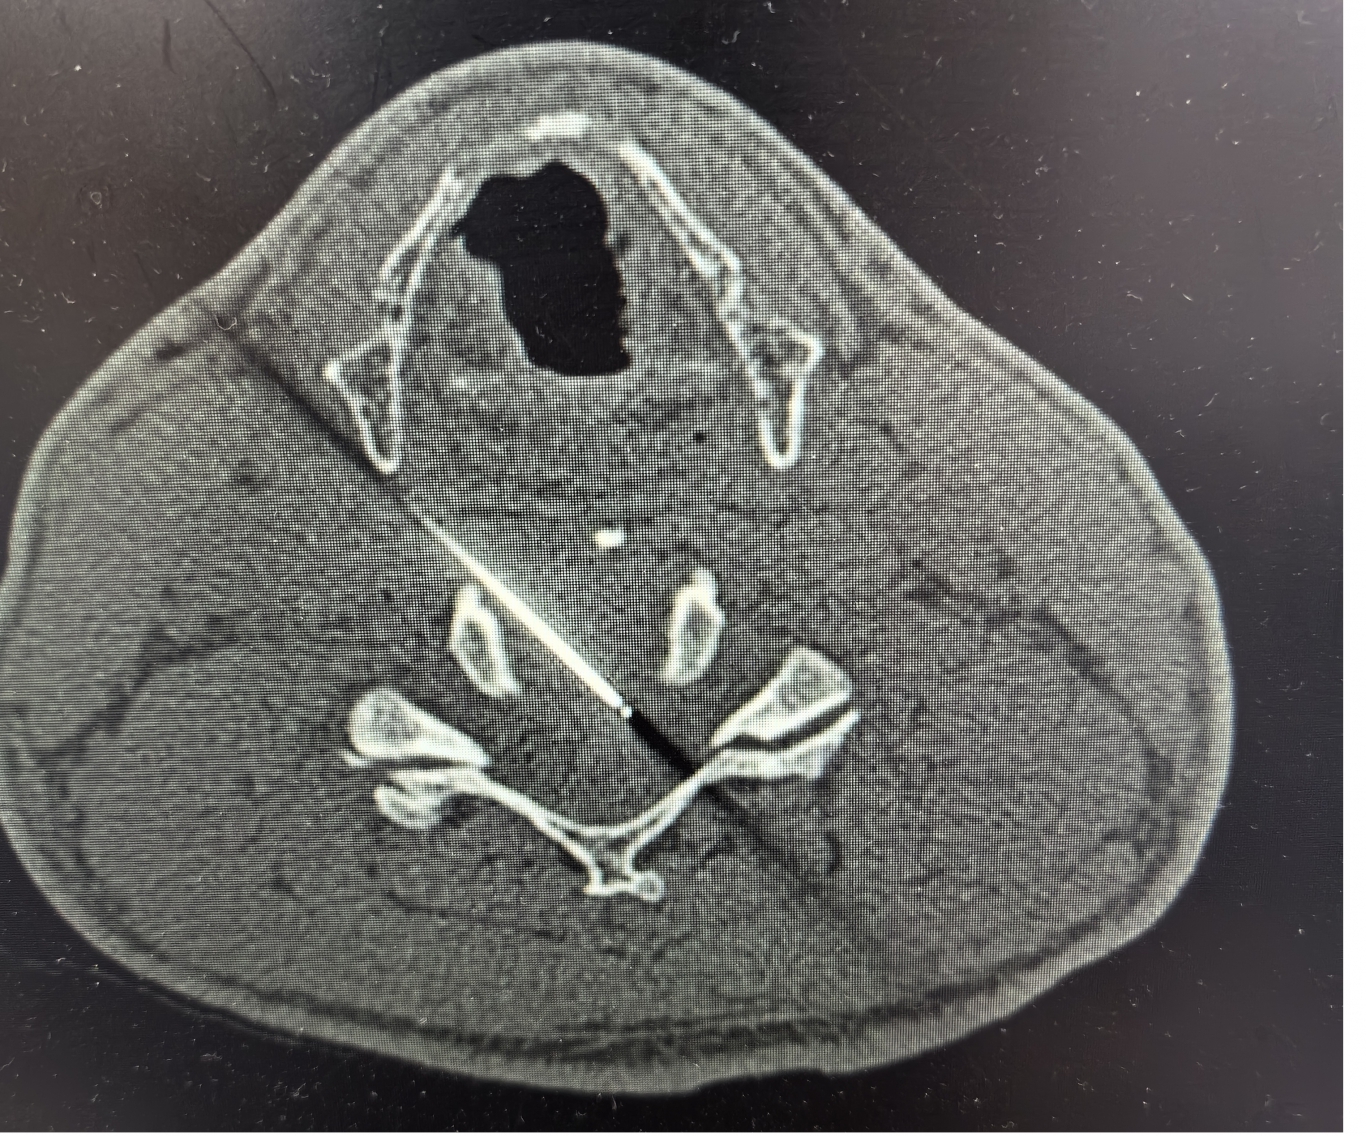

手術之后3天,黃大伯疼痛得到很好緩解,露出了許久沒有的笑容,終于可以安心躺著睡覺了,1個月后基本恢復了正常生活,6個月后復查CT發(fā)現(xiàn)突出的頸椎間盤已經(jīng)基本消失了,黃大伯一家人對治療效果非常滿意。

手術之前CT,巨大突出物 術后6個月復查CT:突出物消失